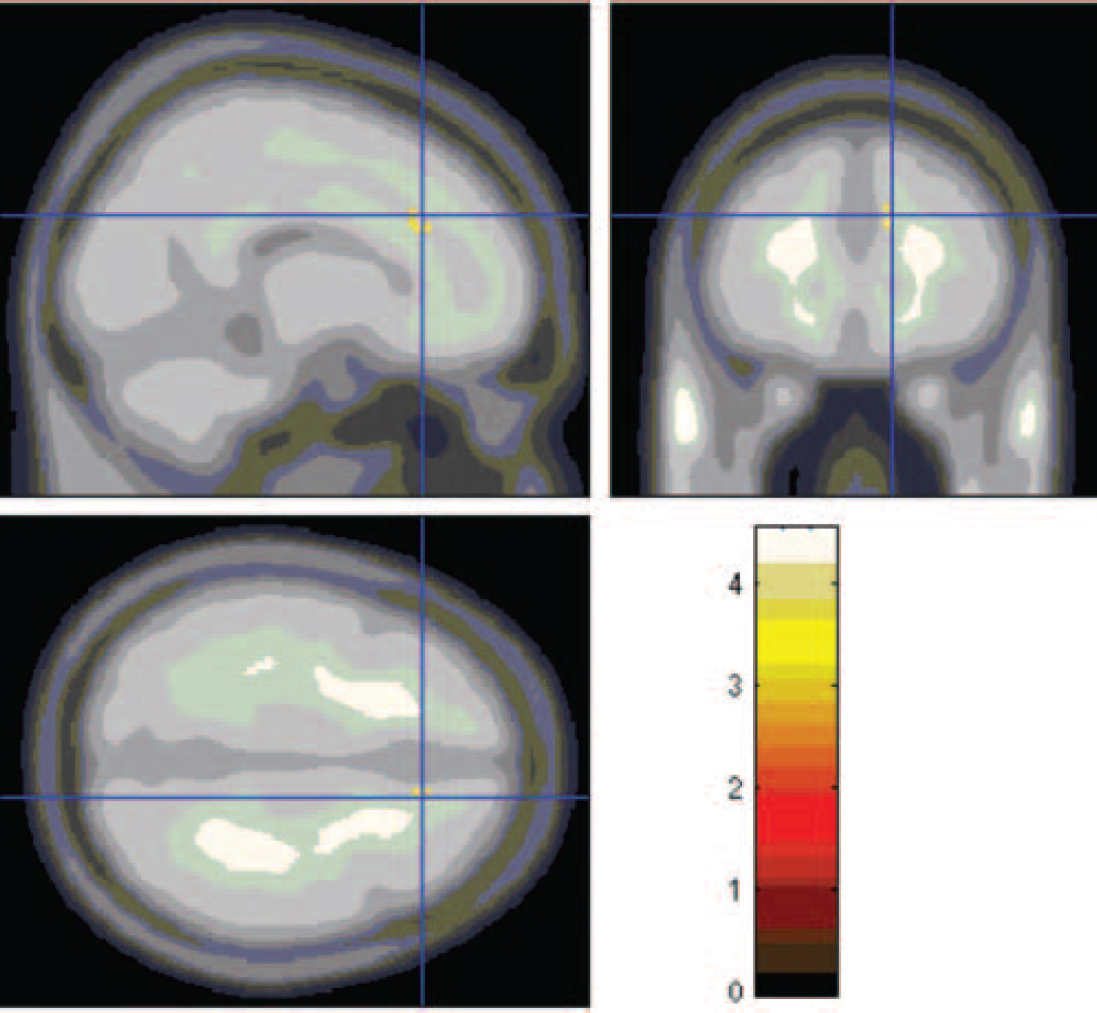

Region of interest analyses. There was one significant difference in peak activation in the right anterior cingulate gyrus (Fig. 3, Table 1) and one nearly significant difference in the left superior frontal/middle frontal gyrus (Fig. 4, Table 1). In both of these areas activations were lower in the alexithymia group compared with the non-alexithymia group.

Fig. 3 Lesser activation in the anterior cingulate cortex, seen in the participants with alexithymia.

Fig. 4 Lesser activation in the superior/middle frontal gyrus, seen in participants with alexithymia.